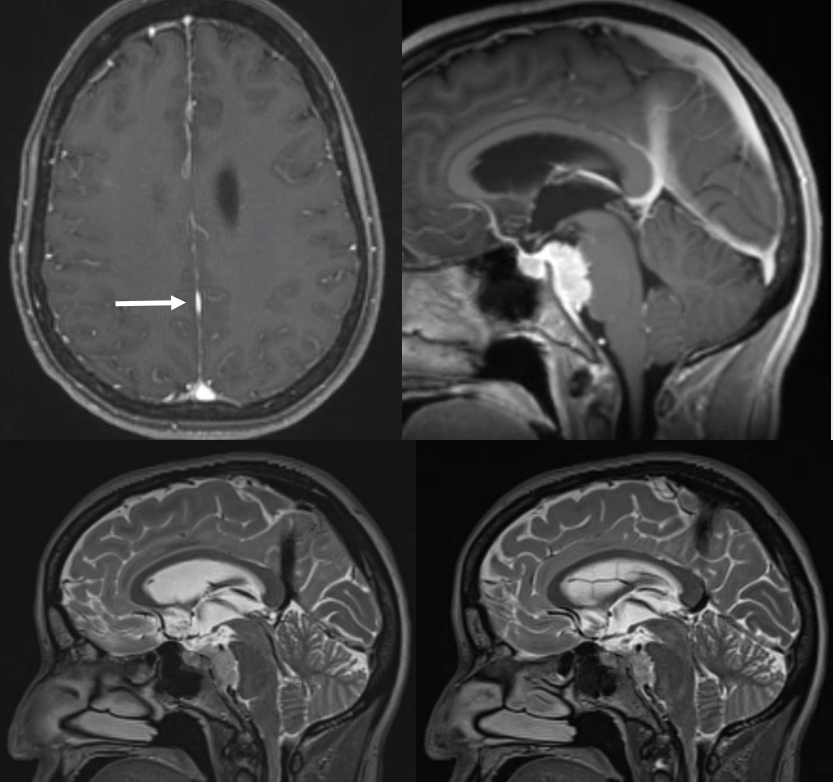

Sagittal Sinus Thrombosis — collaterals.

All of the above anatomic knowledge can become very useful in evaluation of venous thrombosis. Numerous collateral pathways develop in this setting attempting to compensate for the loss. The most dramatic cases usually involve the largest channel — the superior sagittal sinus. In this case, a man presented with what initially was thought to be vasculitis-related brain hemorrhage. Subsequent workup led to an angiogram, where sagittal sinus thrombosis with extensive trans-cerebral and trans-osseous emissary vein collateral channels was seen. In retrospect, these findings were present on the patient’s earlier contrast MRI. “Venovibe” or other contrast-enhanced MR venograms can very sensitive, particularly when interpreted with the appropriate index of suspicion. Noncontrast 2-D time of flight MRV I consider to be next to useless as a problem-solving technique. Any thin-slice postcontrast T1 study is vastly superior.